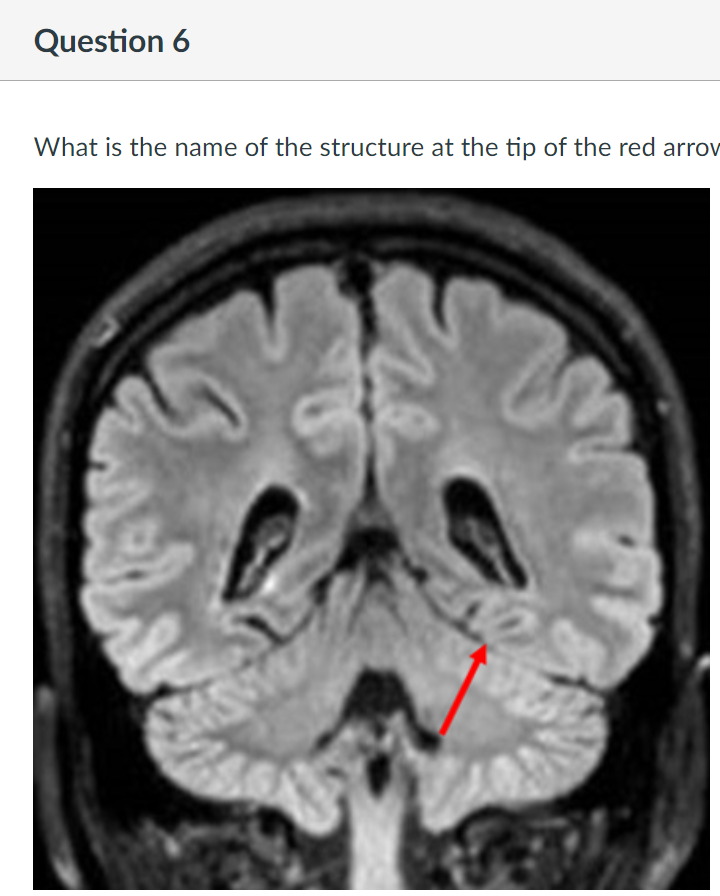

6

Q

A

tentorium cerebelli